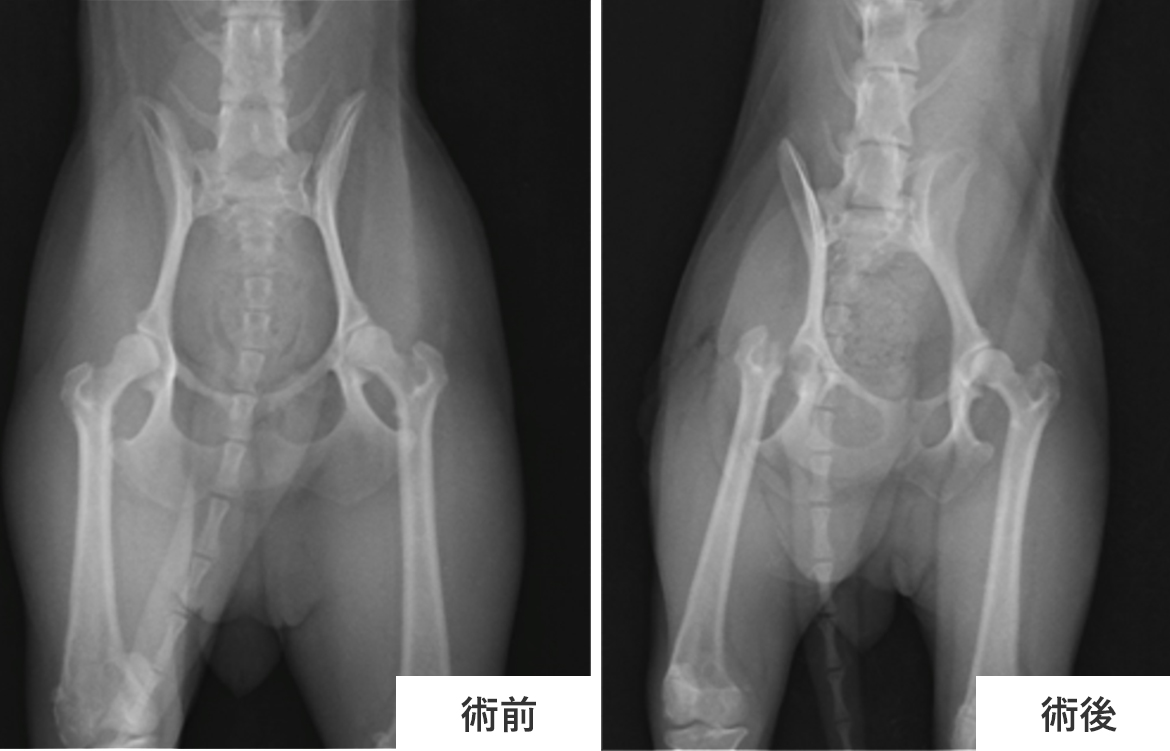

①股関節形成不全に罹患し、右後肢の股関節脱臼が見られたため大腿骨頭頸切除術を実施した1歳のトイ・プードルの術前・術後のX-ray写真です